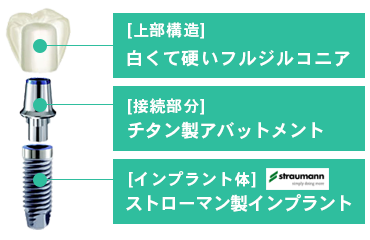

ストローマンはスイスのバーゼルに本社があり、世界70カ国以上500万人以上にインプラントを提供している世界シェアNo.1メーカー。埋入後長期にわたる継続性が高いと研究により報告されている高品質インプラント。当院ではすべてのプランで採用しています。

ストローマン社が研究・開発した、最先端インプラント『ロキソリッド』『SLActive』を使用しています。人体との親和性が高く、インプラント体と骨の早期結合が期待でき、良好な骨質の患者様なら短期間で上部構造を装着することができます。

一般的な治療が終わると、いよいよインプラントの埋入オペを行います。インプラント埋入⇒アバットメント接続⇒上部構造の取り付けと治療は進みます。詳しくは無料相談時に丁寧にご説明いたします。